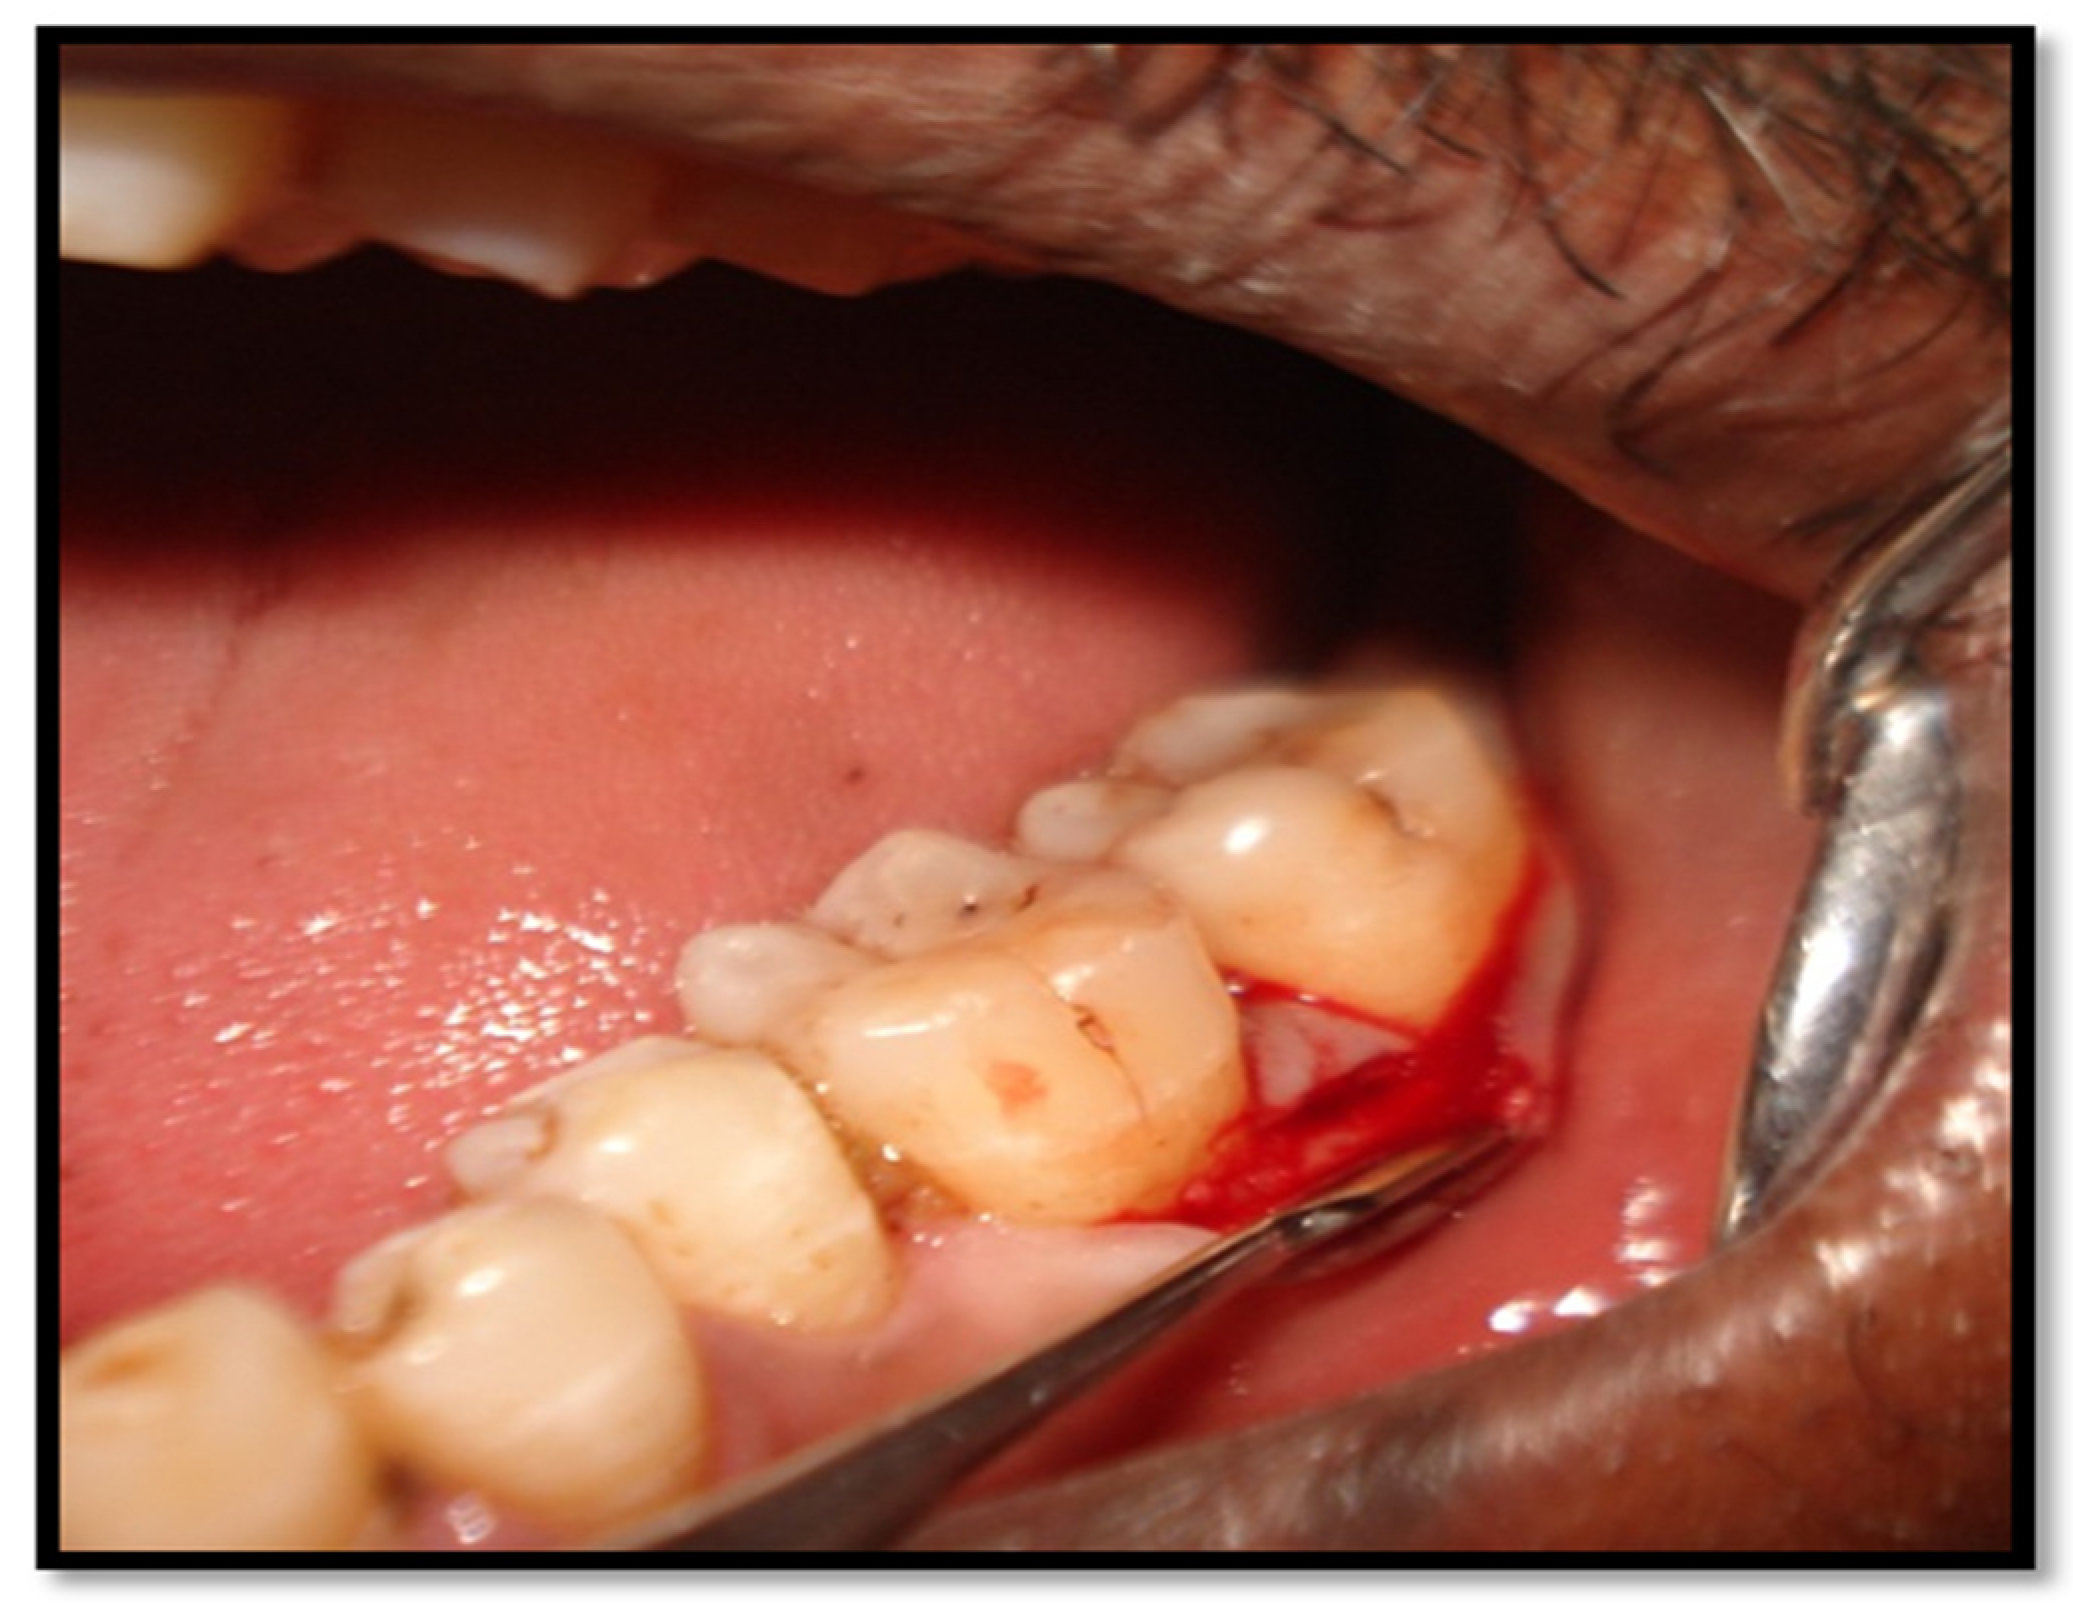

2.4. Surgical Procedures